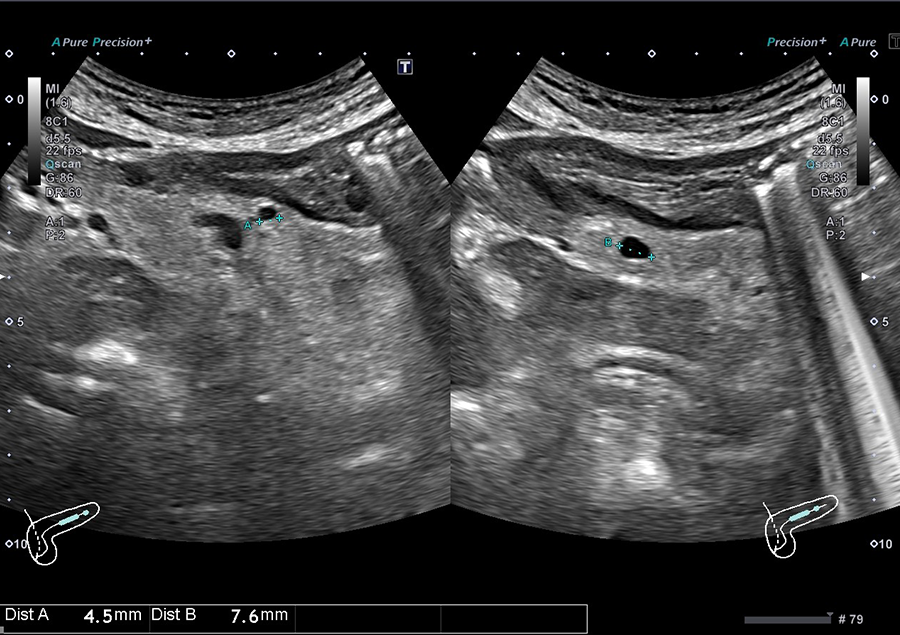

02.最新の超音波診断装置を導入

当院では、キヤノンメディカルシステムズ株式会社の超音波診断装置「Aplio a Verifia」を導入しています。

- ノイズを低減し、クリアな画質で病変を検出

- 従来の腹部エコーに比べ、広範囲を一度に撮影可能で、病変の位置がより分かりやすく確認できます

- 送信・受信技術(Advanced Sync Pulser と Advanced Beam Receiver とMulti-Harmonic Compounding)により、高精細な画像を提供

- 低流速血流の観察に適したSMI で、病変を詳細に観察

高精細な画像と優れた解析技術により、正確に観察することが可能です。